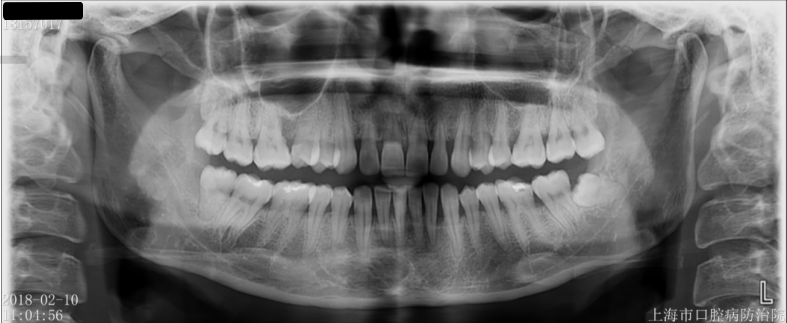

在做任何决定之前,口腔医生会口腔检查,并做X光检查。您可以和口腔医生一起讨论最好的治疗方式。